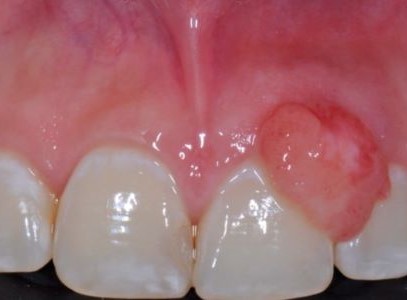

임신성 육아종은 임신 중 잇몸이나 구강 점막에 생길 수 있는 양성 종양(정확히는 화농성 육아종) 입니다.

잇몸 염증(임신성 치은염)이 심한 부위에 잘 생기고

붉은 혹, 혹은 볼록 튀어나온 반점처럼 보이며

자극을 받으면 쉽게 출혈이 생길 수 있습니다.

대부분 출산 후 자연스럽게 줄어들거나 사라지지만,

크기가 크거나

통증이나 출혈이 심한 경우에는

치료가 필요한 경우도 있습니다.